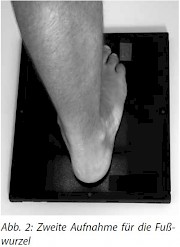

2. Aufnahme (Abb. 2-3)

Nach der 1. Aufnahme bleibt der Patient mit der Fußsohle auf der Kassette stehen und nimmt denanderen Fuß einen Schritt nach vorne. Das Knie der zu untersuchenden Seite leicht anbeugen, damit der Unterschenkel schräg nach vorn geneigt ist und mit der Fußsohle einen Winkel von 45-50° bildet.

Zentrierung: senkrecht über 10° von hinten auf das Fersenbein und Kassettenmitte.

Strahlengang: dorsoplantar Einblenden auf Objekt, d. h. auf das Fersenbein bis zum Unterschenkel

Achtung: Die zweite Aufnahme erfordert bei einem Erwachsenen je nach Konstitution zwischen mind. 3 Belichtungspunkten und 6 Belichtungspunkten mehr Schwärzung!